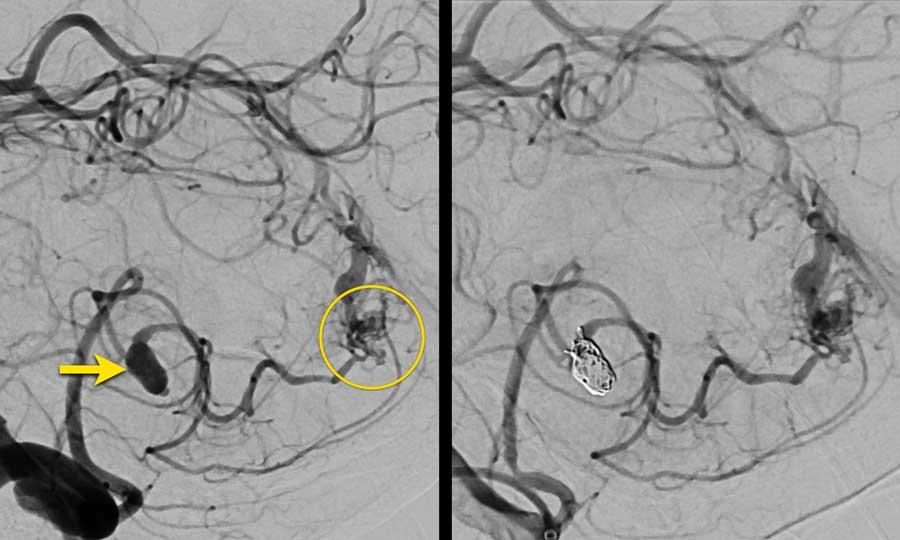

Bệnh nhân nam 65 tuổi với triệu chứng đau đầu khởi phát đột ngột.

NCCT cho thấy xuất huyết dưới nhện hai bên và xuất huyết nhu mô não (mũi tên vàng).

CTA cho thấy tại vị trí xuất huyết nhu mô có một túi phình liên quan đến dòng chảy của động mạch thông trước, được xem là nguyên nhân gây xuất huyết dưới nhện.

Lưu ý khối xuất huyết bên cạnh túi phình (vòng tròn).

CTA cũng cho thấy một AVM với nidus ở thùy trán trái (mũi tên xanh lá).

Ở bệnh nhân có AVM, huyết động học có thể thay đổi theo cách làm suy yếu thành động mạch và dẫn đến hình thành túi phình.

Hình CTA nhìn nghiêng:

- Túi phình liên quan đến dòng chảy kèm túi phình con tại đáy túi phình – mũi tên vàng

- Động mạch nuôi – mũi tên xanh lá

- Nidus AVM – vòng tròn

- Tĩnh mạch dẫn lưu giãn – mũi tên xanh dương

Hình bên trái: DSA túi phình trước điều trị.

Hình bên phải: DSA sau điều trị bằng đặt coil riêng biệt cho túi phình chính và túi phình con (mũi tên vàng).

Quyết định điều trị túi phình trước và phẫu thuật cắt bỏ AVM trong giai đoạn bán cấp khi bệnh nhân đã hồi phục sau xuất huyết dưới nhện.